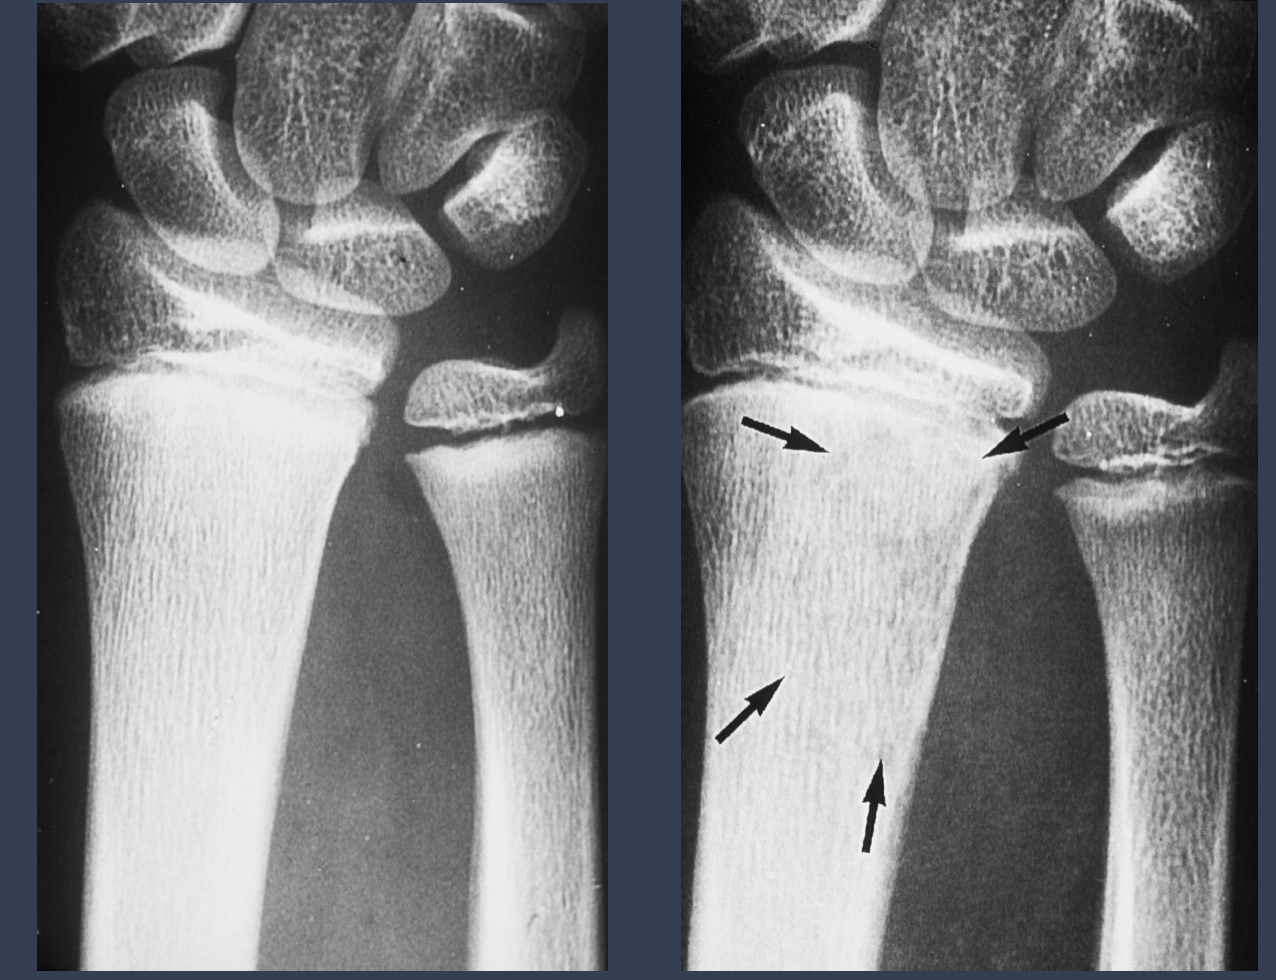

what are the arrows pointing to?

sequestrum = island of dead bone

photo: same patient, repeat xrays

what condition is this?

osteomyelitis

what is the left? what is the right

left: acute osteomyelitis

right: chronic osteomyelitis